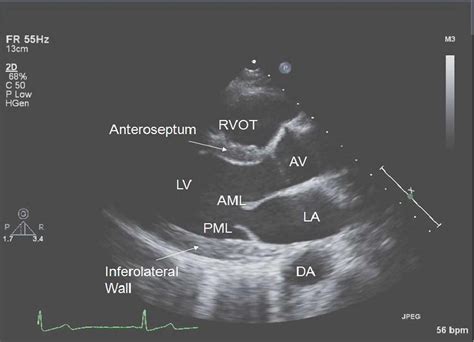

The transthoracic echocardiogram is the most common form of heart imaging. It is a non-invasive, painless procedure where a transducer is placed on the chest wall. The device sends high-frequency sound waves through the skin and chest cavity to visualize the heart's chambers, valves, and surrounding structures.

A transesophageal echocardiogram is a more specialized, semi-invasive imaging technique. In this procedure, a thin, flexible tube (endoscope) with an ultrasound probe at the tip is passed down the patient's throat and into the esophagus. Because the esophagus sits directly behind the heart, this approach provides a much clearer, high-resolution view of cardiac structures that may be obscured by the ribs or lungs during a standard TTE.